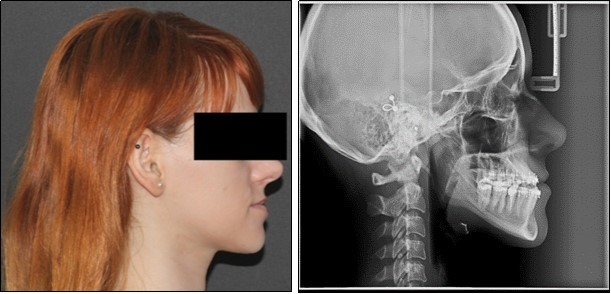

The pre-surgical orthodontic preparation successfully met the following objectives: levelling and aligning, flattening of curbe of Spee, proclination of the lower incisors and elimination of dental compensations. Before surgery, the patient had a normal position of the lower incisors, with IMPA 88 degrees. (Figure 4) Before surgery, a slight anterior open bite and an anterior crossbite could be observed, due to the elimination of dental compensations. Crimpable hooks were placed between each tooth on the 0.019x0.025 SS archwires, to allow placement of intermaxillary elastics after surgery. (Figure 5).

Figure 4.Pre-surgical extraoral photographs, after orthodontic preparation and preoperative lateral cephalometric radiograph